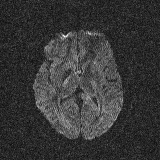

Refer to caption

(a) b = 0 s/mm2

(b) b = 1000 s/mm2

(c) b = 4000 s/mm2

Figure 3: Example axial slice from the STE brain dMRI, involving b-values of 0, 1000 and 4000 s/mm2.

2.6 Brain dMRI by spherical b-tensor encoding

We reused the dataset described in [24]. Images were acquired using the MAGNETOM Prisma 3T (Siemens Healthineers, Germany) system. A research pulse sequence was used [25]. One volunteer was enrolled. However, as the original paper was targeted at dMRI super-resolution reconstruction, eight volumes were acquired with differently rotated fields of view. Namely, the FOV was rotated about the anteroposterior axis, starting in the axial orientation, and then at angles of 22.5, 45, 67.5, 90 (sagittal), 112.5, 135, 157.5 degrees. b-values of 0, 1000 and 4000 s/mm2 were used with 2, 4 and 15 repetitions, respectively, for each field of view. The images have 1.58×\times×1.58×\times×7.2 mm3 voxels and matrix size of 132×\times×132×\times×26. An example slice is shown in Figure 3.